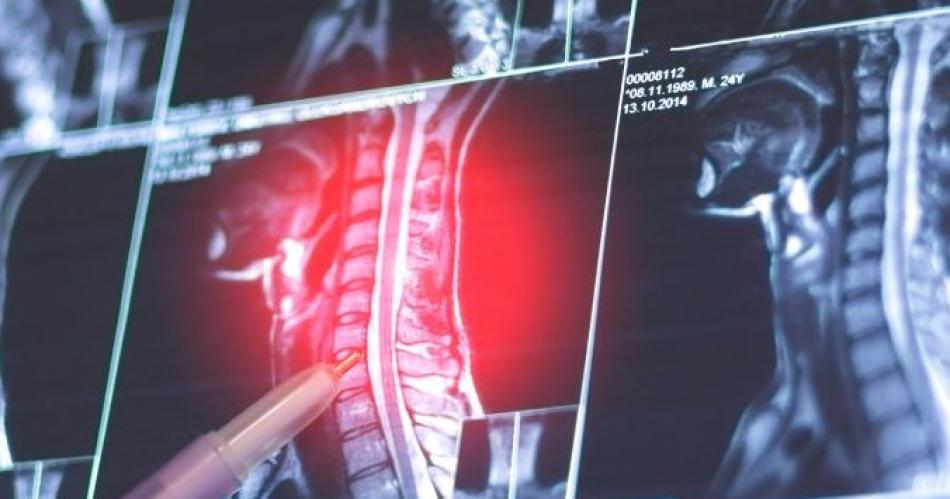

En tanto, aproximadamente el 40% se localiza en la columna, generalmente afectando a las estructuras posteriores vertebrales. Esta localización, señalan desde la asociación contra el cáncer, "puede asociarse a escoliosis y a síntomas neurológicos", de ahí la importancia de detectarlo a tiempo para tratarlo.

Para diagnosticar los osteoblastomas, los especialistas realizan radiografías y otras pruebas de diagnóstico por imagen como tomografía computarizada (TC) y resonancia magnética nuclear (RMN). "Para confirmar el diagnóstico de osteoblastoma, además, se toma una muestra de tejido y lo examina al microscopio (biopsia)", señalaron los expertos.

Los signos y síntomas de los tumores vertebrales más frecuentes son: dolor de espalda en la zona del tumor; dolor de espalda que se irradia o dispara desde la espalda a una zona cercana; dolor de espalda que empeora por la noche; cambios en la sensibilidad, como entumecimiento o sensación de pinchazos; pérdida de la capacidad de mover parte del cuerpo; pérdida de control sobre la vejiga y los intestinos; debilidad muscular.